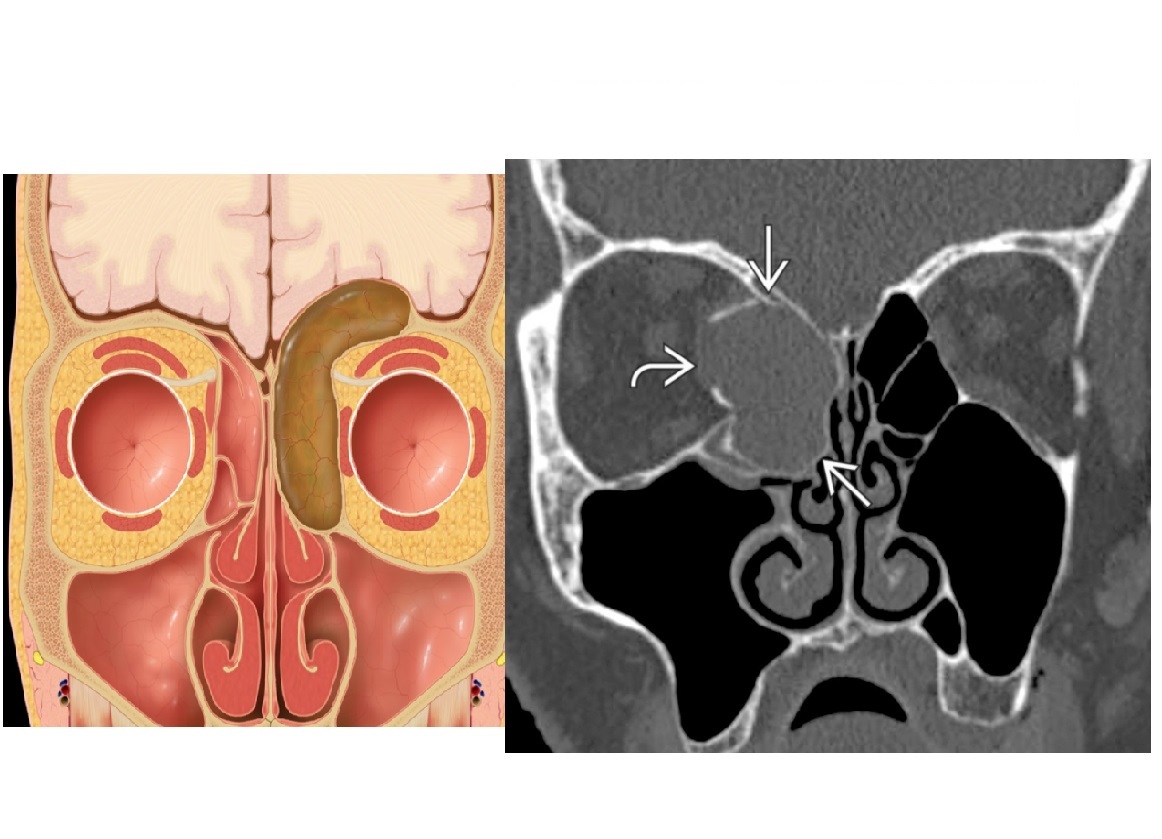

Complete opacification of the maxillary sinus, peripheral enhancemen, expanded sinus with smooth remodeling of walls?

A

Mucocoele

Nb - Ostium of given sinus is occluded thus complete opacification.

*- Doesn’t extend beyond the cavity. *

- **Expands cavity and can cause bone thinning. **

Associated with* CF and prior trauma*

Peripheral enhancment allows differentiate from neoplasm

Low attenuation mass in the sinus that expands the cavity and extends into the meatus ?

Antrochonal polyp/Solitary Sinonasal Polyp

*Nb - T2 bright and also peripheral enhancement. *

Typically doesn’t completely opacify the sinus

Solitary ‘dumbell shaped-‘ polypoid mass fills maxillary antrum, then spills through enlarged maxillary ostium and infundibulum or accessory ostium into nasal cavity